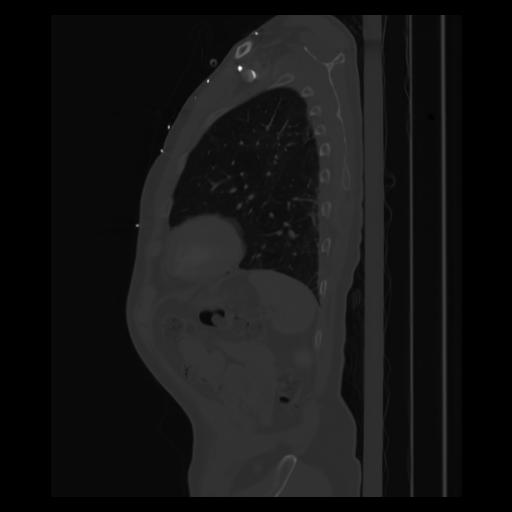

30 CUERPO,CE,Sagittal,3.000,CUERPO,Sagittal,